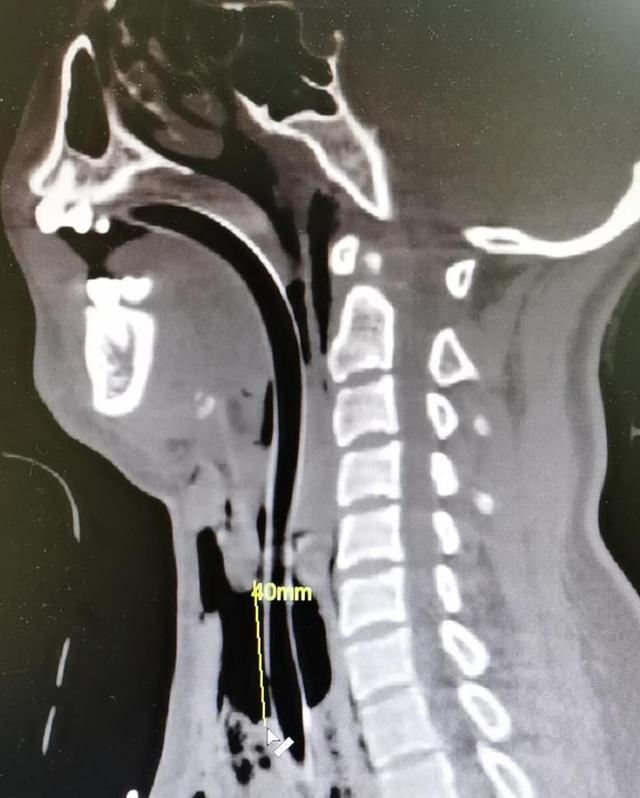

“我们考虑 , 应该是被勒了以后引起的颈部损伤 , 有可能有血肿、水肿 , 所以说后来考虑到安全问题就给她气管插管 , 但是插管的过程中发现气管破了 , 最长的缺口有4厘米 。 ”

当天 , 小郭就做了长达5个小时的手术 。 “气管切开之后对缺口进行了处理 , 现在还有一个气管套套在这里 。 刚刚手术 , 有可能还会引起一些感染的并发症 , 像肺部的感染等等 , 这些后续的感染需要预防 。 ”谢天舜说 。